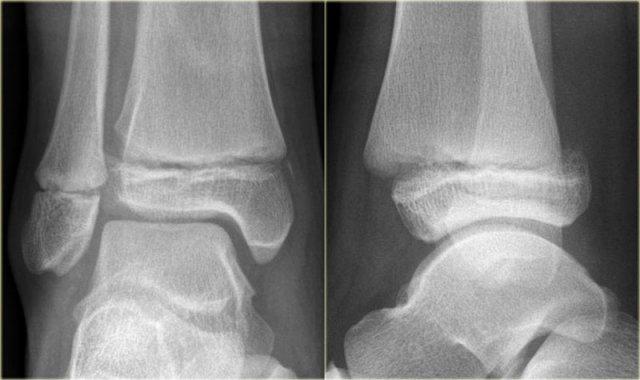

- Nhận định ban đầu

Có gãy xương mắt cá sau.

Không thể phân loại theo Weber.

Gãy xương mắt cá sau đơn độc là không phổ biến, nhưng khi là một phần của chấn thương sấp-xoay ngoài (Weber B) hoặc ngửa-xoay ngoài (Weber C) thì khá thường gặp.

Do đó, chúng ta cần xem lại phim để tìm kiếm các dấu hiệu của gãy xương Weber B hoặc C.

- Đánh giá lại

Không có dấu hiệu gãy xương chéo ở mắt cá ngoài, do đó có thể loại trừ gãy xương Weber B.

Vẫn còn khả năng gãy xương Weber C, bao gồm: đứt hoặc bong gân phía trong, gãy xương mác cao và cuối cùng là gãy xương mắt cá sau.

Lúc này chúng ta chú ý thấy hình ảnh bong gân nhỏ tinh tế ở mắt cá trong (mũi tên đỏ).

Phim X-quang bổ sung của chi dưới cho thấy gãy xương mác cao (mũi tên xanh). - Kết luận cuối cùng

Gãy xương Weber C giai đoạn 4.